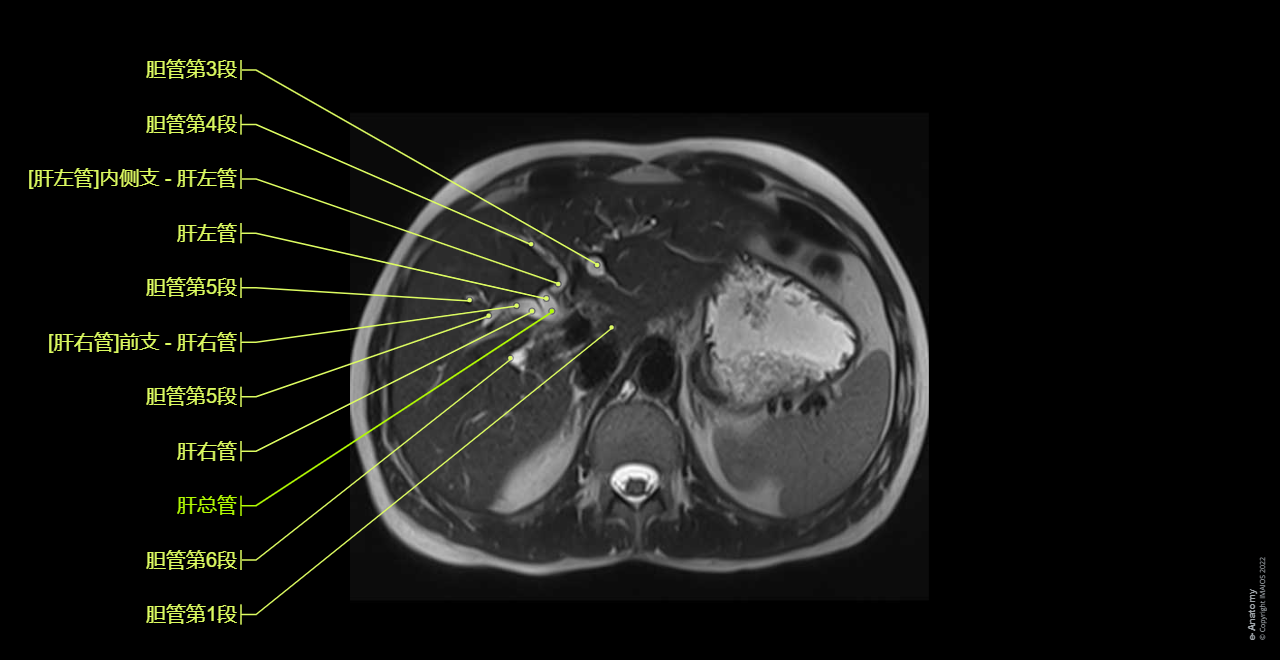

To emphasize our pedagogic goal in anatomy, we did not choose a healthy patient where the thin (not dilated) biliary tree may have been difficult to see on MRI, but a patient with dilated biliary tree (intrahepatic ducts and common bile duct) on a choledocholithiasis (gallstone) of the distal common bile duct.

Note that in the case displayed in this module, the patient presents a small anatomical variation of the biliary tree anatomy, type IIIA (the right posterior hepatic duct draining into the left hepatic duct (see diagram below)).

Axial T2 HASTE: Axial breath-hold T2-weighted turbo spin-echo (TSE), 5 mm slices, on the whole biliary tract. Two breath-hold acquisitions are obtained so that the whole of the liver down to the duodenal ampulla is visualized.

MRCP thick slab (T2 weighted breath-hold HASTE fat-saturated thick slab): A fat saturated HASTE sequence where a single slab of data 4 cm in thickness is acquired in a 1- to 2-s breath-hold in 3 different coronal planes. MIP images have also been displayed.

Axial T2 HASTE 4 mm on CBD: An axial breath-hold T2-weighted turbo spin-echo (TSE), 4 mm slices only on the dilated common bile tract.